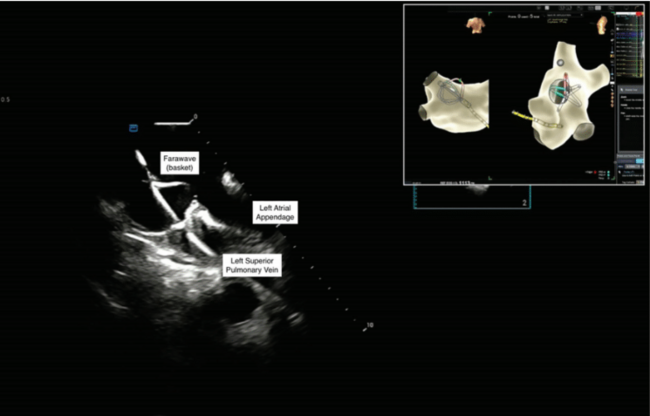

Through the transseptal sheath, detailed mapping of the LA using a multipolar catheter (Advisor HD Grid Mapping Catheter, Sensor Enabled, Abbott) was performed to define anatomy and baseline endocardial voltage, which was normal in this case. The Farapulse catheter was then advanced into the LA over a J wire, which was clearly visible with ICE in the LA. The wire was also pinned directly into the EAM to allow visualization of its tip without fluoroscopy.4 The wire was sequentially advanced into each PV and used to advance the ablation catheter in both “basket” and “flower” configurations up to the ostia and antrum of each vein, respectively, for PFA applications (Figures 1 and 2, Videos 2-4). The ICE catheter enabled undoubtful confirmation of adequate tissue contact of the splines of the ablation catheter, appropriately centered position in each vein, and dynamic surveillance of appropriate wire positioning.

The evaluation of transseptal puncture position and pre- and post-procedure assessment for pericardial effusion are similar to techniques used previously in RF ablation. However, the monitoring of positioning and shape of the PFA catheter are new challenges. These are further heightened by the potential use of EAM systems that are not inherently designed to visualize the PFA catheter with the degree of reproducibility and accuracy that electrophysiologists are accustomed to in RF ablation. When the PFA catheter, sheath, and wire are not sensor-enabled, it becomes more critical to have a second tool for visual feedback. In our experience, advancing the ICE catheter to the LA allows for high-definition detailed imaging with the best possible visual confirmation of these components as well as detailed anatomical assessment. While conventional ICE imaging from the RA can be used, image definition is much less precise and there are often artifact/interference issues from the interatrial septum, especially to appropriately visualize the right PVs. Positioning in the LA overcomes these issues and allows for more consistent near-field views of the sheaths and catheters.

While much of the additional value of ICE relates to enhancing safety, there are also considerations regarding the efficacy of ablation when using ICE to visualize the PFA catheter prior to lesion delivery. It has been shown that direct tissue-catheter contact contributes to the depth of PFA lesion formation.5,6 Without direct visualization, the ability to achieve consistent tissue contact in the absence of fluoroscopy relies on the tactile sensation of the operator or the accuracy of the EAM in projecting catheter position. Conversely, with ICE positioned in the LA, the opposition of the PFA catheter splines to the tissue can be easily and undoubtfully confirmed prior to lesion application in the PVs as well as along the roof, ridge, and posterior wall, allowing precise and consistent high-quality lesion formation.